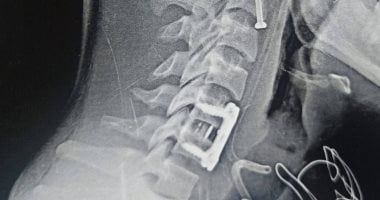

استقبال المريض بالمستشفى بإصابات بالغةوتابعت المستشفي، أنه استقبل قسم الاستقبال والطوارئ بالمستشفيات مريضاً إثر سقوطه من علو، وبالفحص الدقيق تبين وجود كسر بالفقرة العنقية الثانية، وهو موقع شديد الخطورة لقربه من "جذع المخ" مركز العمليات الحيوية والحبل الشوكي، حيث كشفت الأشعة عن تزحزح فقاري بين الفقرتين الخامسة والسادسة.

تجهيز المريضة وإجراء جراحة عاجلةوأكدت، أنه تم إجراء الجراحة تحت إشراف وتوجيه الدكتور إسلام أبو الفتوح رئيس قسم جراحة المخ والأعصاب، والدكتور إيهاب سعيد رئيس قسم التخدير، حيث تمكن الفريق الطبى من تثبيت كسر الفقرة العنقية الثانية بدقة متناهية، وتثبيت التزحزح الفقاري الخامسة والسادسة باستخدام شريحة ومسامير وقفص عنقي.